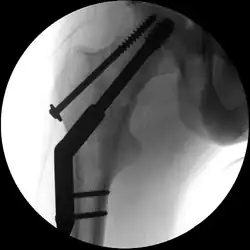

Laterale Schenkelhalsfraktur mit Adduktions/Varus-Fehlstellung

Intraoperative Durchleuchtung (C-Bogenaufnahme) nach Osteosynthese einer lateralen Schenkelhalsfraktur mittels dynamischer Hüftschraube und zusätzlicher Antirotationsschraube